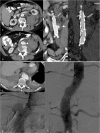

Objectives: To demonstrate the various presentations of acute aortic pathology and to present diagnostic and therapeutic approaches.

Methods: Diagnostic imaging is the key to the reliable diagnosis of acute aortic pathology with multi-slice computed tomography angiography (CTA) as the fastest and most robust modality. Endovascular aortic repair (EVAR) with stent grafts and open surgical repair are therapeutic approaches for aortic pathology.

Results: CTA is reliable in diagnosing and grading aortic trauma, measuring aortic diameter in aortic aneurysms and detecting vascular wall pathology in acute aortic syndrome and aortic inflammation. CTA enables planning the optimal therapeutic approach. Stent graft implantation and/or an open surgical approach can address vascular wall pathology and exclude aortic aneurysms.

Conclusion: Aortic emergencies have to be detected quickly. CTA is the imaging method of choice and helps to decide whether elective, urgent or emergent treatment is necessary with EVAR and open surgical repair as the main treatment approaches.

Teaching points: • To present aortic pathology caused by trauma • To present acute aortic syndrome (aortic dissection, intramural haematoma and penetrating ulcers) • To present symptomatic and ruptured aortic aneurysm • To present infection (mycotic aneurysms/aorto-duodenal fistulae) or iatrogenic injury of the aorta • To understand different presentations for treatment planning (EVAR and open surgery).